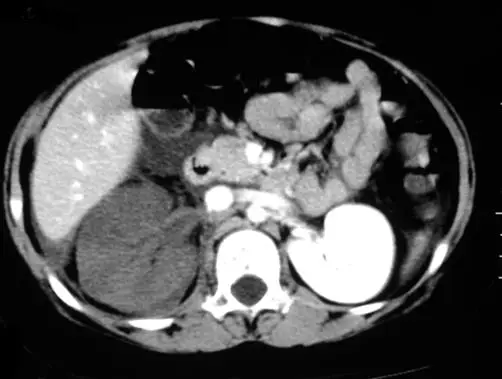

10 歲女生因發高燒不退、劇烈右側腰痛而住院,注射對比劑後的電腦斷層掃描影像如圖,下列原因何者最為可能?

圖片為腹部軸向(axial)CECT 影像。影像右側可見左腎(增強良好,呈均勻高密度),影像左側(患者右側)可見右腎呈現明顯的楔形低密度缺損(wedge-shaped hypodensity),病灶由腎門向腎皮質外緣延伸,呈三角形或楔形分布,範圍廣泛,幾乎涵蓋右腎大部分實質。與對側正常強化的腎臟相比,右腎幾乎完全無法被對比劑充分灌注,提示嚴重的腎臟血流灌注障礙。此楔形低灌注型態是**腎動脈栓塞(renal artery embolism)或腎梗塞(renal infarction)**最具特徵性的影像表現。主動脈及腔靜脈可見強化。